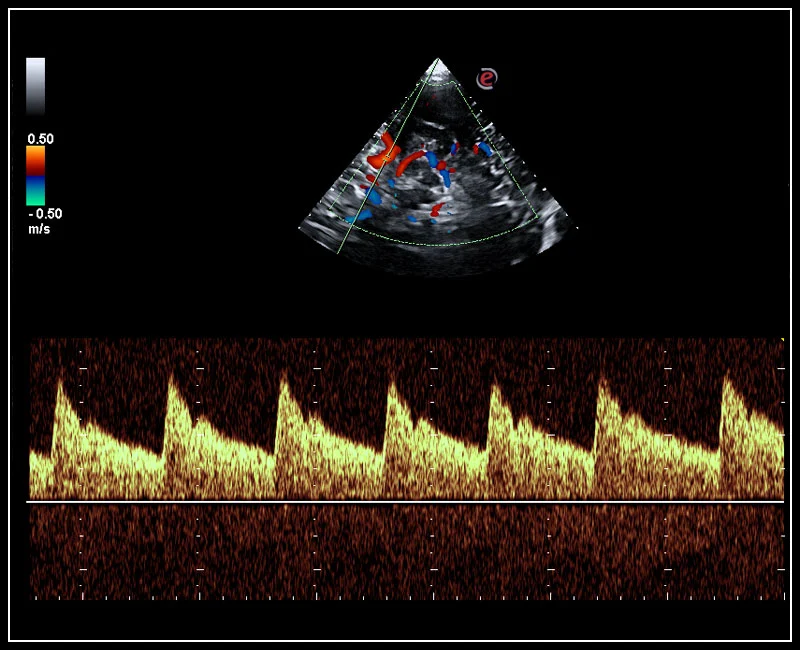

MyLab™X5 - Stress echo

MyLab™X5 - Stress echo